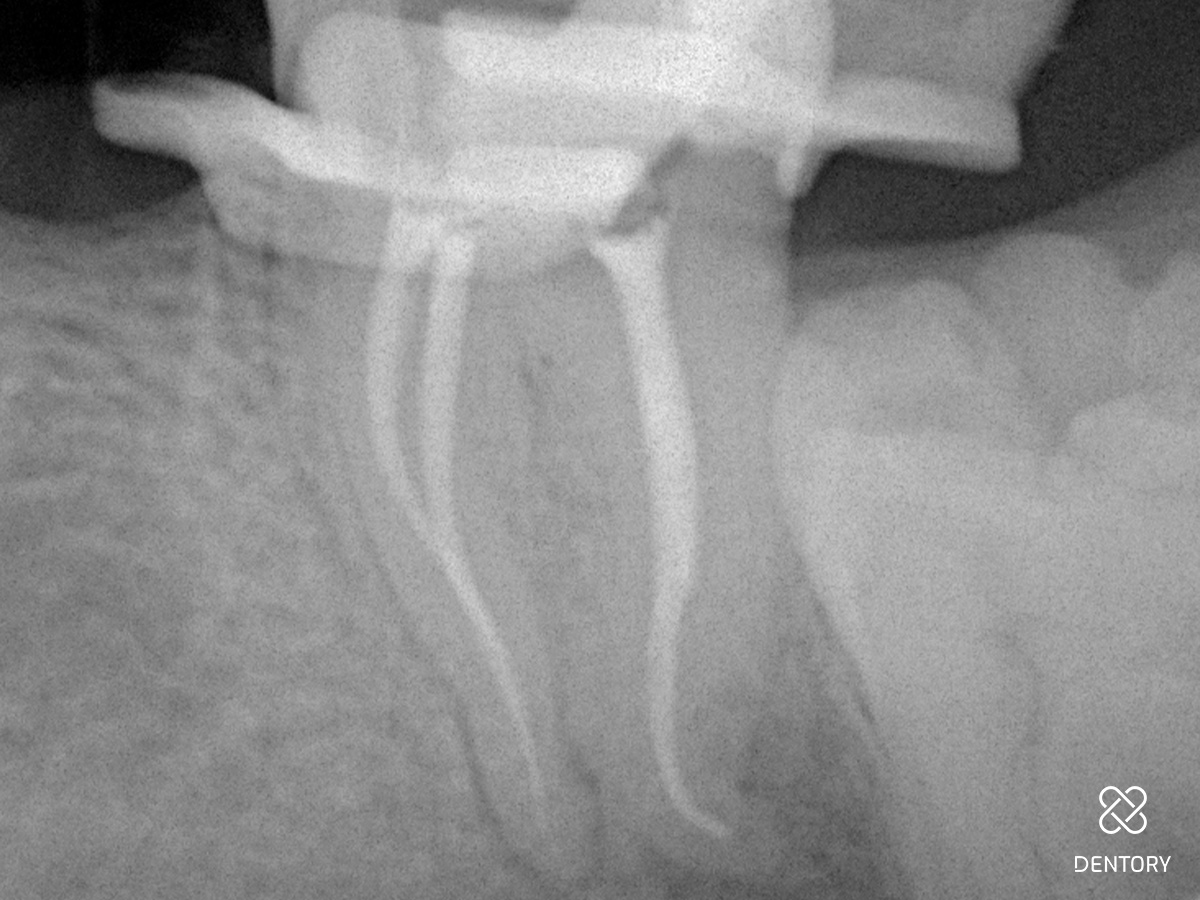

Abbildung 3

Aufbereitung des distalen Kanals: Es ist darauf zu achten, die Kontaktzeit im Kanal kurz zu halten sowie den Kanal abschnittsweise von koronal nach apikal zu bearbeiten. Zusätzlich verhindert eine regelmäßige Rekapitulation mit einer Handfeile bis zur endometrisch bestimmten Länge eine Verblockung des Kanals mit Debris.